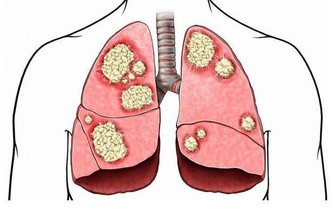

肺是人體極其重要的呼吸器官,是體內氧氣循環的關鍵。不過,現代很多人存在不良的生活和飲食習慣,比方說,時不時抽煙喝酒,動不動就熬夜……導致肺部功能或多或少受損,影響身體健康。那麼,肺好不好,可以通過哪些方法判斷?冬季養肺應該怎麼做?

肺好不好,不妨看看5個地方

1、睡眠

如果在沒有感冒的情況下,睡覺前反复咳嗽,並且存在胸悶、胸痛的情況,就要考慮是否肺部出現問題,有可能是肺炎所致。

2、呼吸

一般來說,如果人的肺部功能下降,那麼呼吸就會不規律,如變得急促或變得衰弱等,有時需要深呼吸才可以獲取足夠的氧氣。

所以,想知道自己的肺好不好,可以通過自身的呼吸情況判斷,具體將手指放在鼻孔下方,觀察呼吸是否均勻、正常即可。若是有呼吸困難、急促的現像出現,有可能是肺部出現病變,需要多加重視。

3、嘴唇

要想判斷肺部功能狀況,還可以通過嘴唇。如果肺部功能不好,那呼吸就可能受阻,進而導致血液中氧氣不足,最終導致嘴唇顏色發生改變。

其中,健康人的嘴唇是紅潤的;而肺部有異常的人,嘴唇則多呈現出青紫色。

4、皮膚

肺部功能正常的人,在有足夠氧氣的提供下,皮膚會呈現出紅潤的狀態,看起來很健康;相反,肺不好的人,氧氣供給不足,皮膚狀態會變差,一眼看上去會十分蒼白。

5、手指

不少存在嚴重肺部疾病的人,會出現杵狀指的情況,較為常見的就是手指頭增生粗大。

因此,想判斷肺部功能好不好,也可多觀察手指。若是手指粗細均勻,沒有指頭粗大現象,就說明肺部功能良好;而若是已經出現杵狀指,就可能是肺部病變了,建議及時就醫。